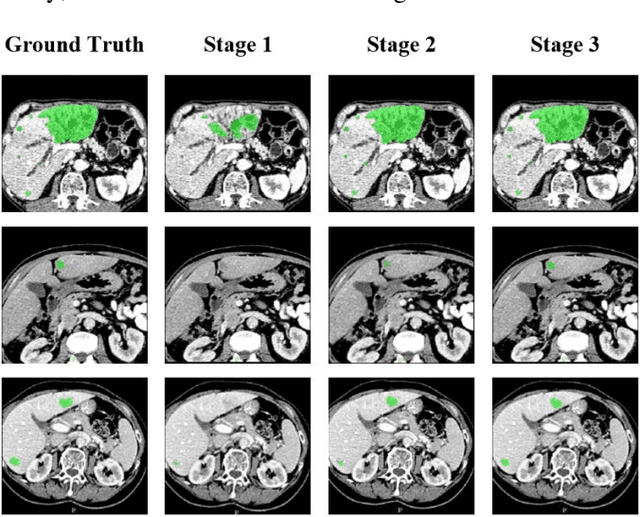

Abstract:Automatic segmentation of liver tumors in medical images is crucial for the computer-aided diagnosis and therapy. It is a challenging task, since the tumors are notoriously small against the background voxels. This paper proposes a new three-stage curriculum learning approach for training deep networks to tackle this small object segmentation problem. The learning in the first stage is performed on the whole input to obtain an initial deep network for tumor segmenta-tion. Then the second stage of learning focuses the strength-ening of tumor specific features by continuing training the network on the tumor patches. Finally, we retrain the net-work on the whole input in the third stage, in order that the tumor specific features and the global context can be inte-grated ideally under the segmentation objective. Benefitting from the proposed learning approach, we only need to em-ploy one single network to segment the tumors directly. We evaluated our approach on the 2017 MICCAI Liver Tumor Segmentation challenge dataset. In the experiments, our approach exhibits significant improvement compared with the commonly used cascaded counterpart.